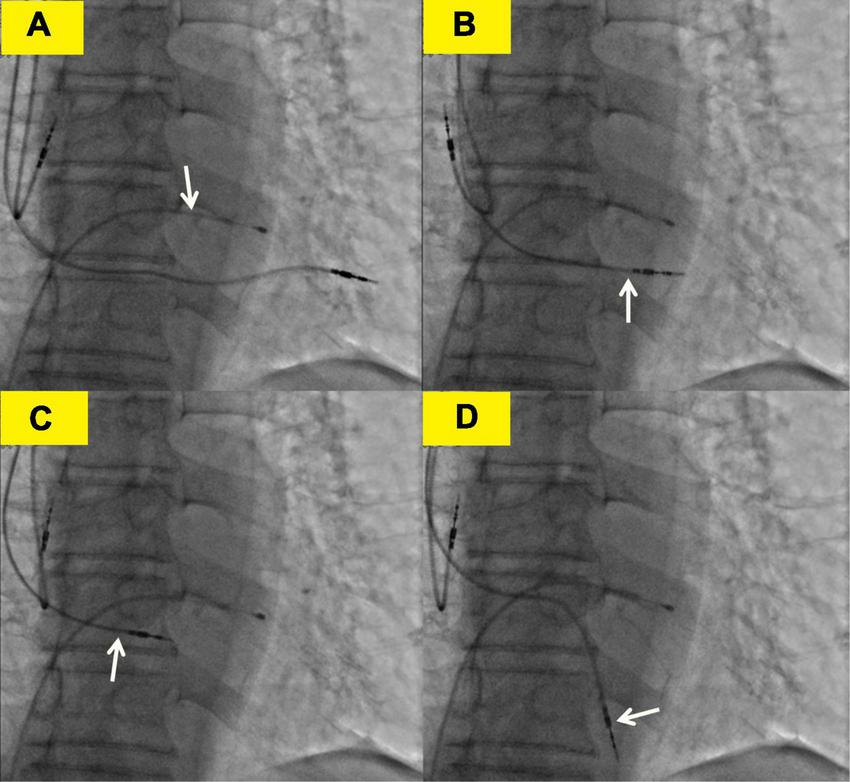

FIGURE 3

Transvenous lead extraction process. (A) The white arrow shows the lead of the temporary transvenous pacemaker. (B) The white arrow shows the right ventricular (RV) lead was screwed back to the left ventricle. (C) The white arrow shows the RV lead was screwed back to the right ventricle. (D) The white arrow shows the right ventricular lead was refixed at the lower right ventricular septum.

The subsequent patient’s management was thoroughly debated. Patients may not tolerate surgical lead extraction due to the variety of severe chronic diseases and advanced age. Therefore, on the 5th POD, we performed transvenous lead extraction under transesophageal echocardiography monitored and cardiac surgery backup. Figures 3A–D depict and describe the entire procedure in detail. Transvenous lead extraction was uncomplicated and did not have any hemodynamic instability, and intraoperative ultrasonography monitoring showed no increase in pleural effusion and pericardial effusion. The original RV lead was refixed at the lower RV septum to reduce the risk of perforation and consequent tamponade. Subsequent electrocardiogram and PM interrogation revealed the PM functioning normally with excellent pacing parameters (intraoperative RV lead impedance and threshold were 1,020 Ω and 1.0 V, respectively) (Figure 1D). On the 10th POD, the patient was discharged, and the subsequent 6 months of follow-up were uneventful.